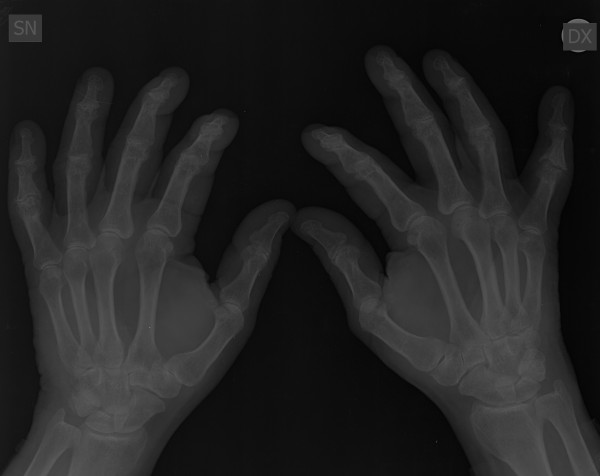

Mi piacerebbe avere un ulteriore parere sulla radiografia alle mani che allego anche per una eventuale cura da seguire. Grazie!!

0006B312.jpg

[ 24.9 KiB | Osservato 1617 volte ]

0006B311.jpg

[ 27.61 KiB | Osservato 1617 volte ]

0006B310.jpg

[ 32.51 KiB | Osservato 1617 volte ]

Non ha senso un parere del reumatologo quando esiste un referto del radiologo. Il problema potrebbe nascere se il quadro clinico e/o di laboratorio fossero in disaccordo con i dati radiologici. E' solo dal confronto dei 3 elementi (clinico in primis, poi radiologico e di laboratorio) che si può azzardare una diagnosi e quindi impostare un trattamento. Le macchine finora non sostituiscono del tutto il medico.